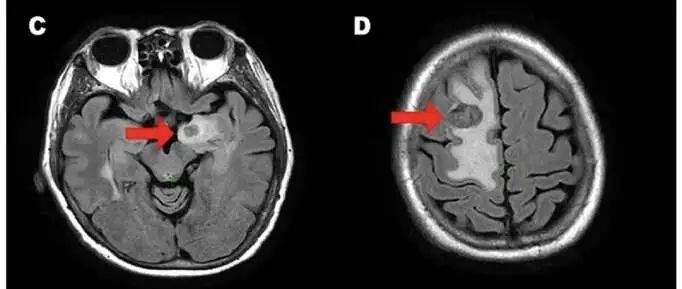

该做的治疗也做了,本以为自己这次终于可以和乳腺癌做最后的告别,但在2022年10月,我的病情再次出现进展,脑部MR检查发现“多发脑转移灶”。

图3 脑MR提示脑内多发转移

面对第三次复发转移,我的反应平静得自己都惊讶。或许是因为生活给我的选项从来就只有一个:继续战斗。

医生推荐了新型靶向药DS-8201,这是一种针对HER2低表达转移性乳腺癌患者的抗体偶联药物。用药后,我的病情很快稳定了下来。这无疑给了我一针“强心剂”,坚定了我继续与病魔斗争的勇气。

2023年8月,为了进一步控制脑部病灶,我接受了全脑放疗+局部加量放疗。治疗过程中,我曾出现轻度肢体无力和脑水肿,但在医生的对症治疗后症状得到很好缓解。

目前,我的脑部肿瘤有所缩小,精神状态也不错。 计划继续DS-8201维持治疗并定期复查。